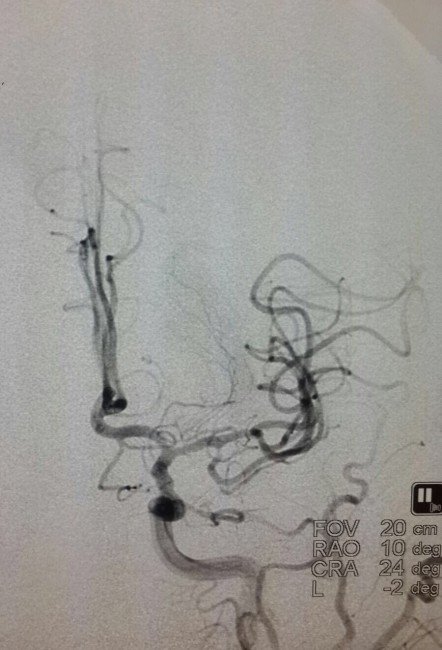

İnme hastalığı ve Sezer'in durumu ile ilgili detaylı bilgi veren Girişimsel Radyoloji Uzmanı Doç. Dr. Çağın Şentürk de şunları söyledi: "Hastanın beyninin sol tarafına pıhtı nedeniyle hiçbir şekilde kan ulaşmıyordu. Biz bu pıhtının içerisinden geçip özel bir stent yardımı ile beynin normal kısmına ulaştık ve pıhtıyı çıkardıktan sonra kan gitmeyen bölgeyi normale döndürdük. Hastamız konusundaki en büyük korkumuz zamandı. Zaman bu işlemlerde çok önemlidir. Altı saati geçtikten sonra risk almaya başlıyorsunuz. Hastamız için karar almak bizim için zordu. Burada süre ile birlikte radyolojik görüntüleme de çok önemli. Radyolojik inceleme sırasında beynin ne kadarlık kısmının kansız kalıp etkilendiğini belirledik ve kurtarılabilecek olan beyin dokusunun ne kadar önemli olduğuna karar verdik. Uygun görüntüleme yöntemi ile beyinde hâlâ kurtarılabilecek alan olduğunu tespit ettik. Pıhtı çıkarma işleminden sonra hastamız neredeyse tamamen iyileşti."